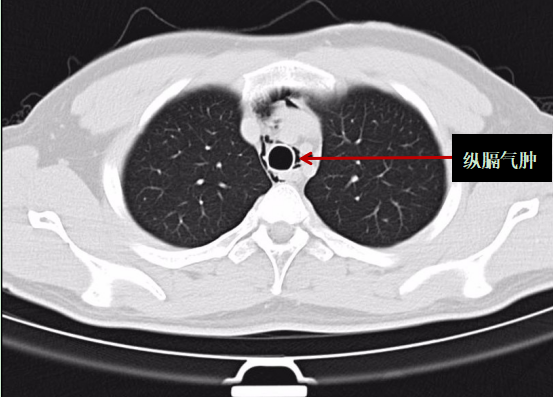

深圳市人民医院急诊科医生给阿岳做了诊察后,建议阿岳立马做一个胸部CT查看具体病情。当阿岳的胸部CT报告出来后,他立马被转到了抢救室进行治疗。

医生表示:根据胸部CT报告,阿岳被诊断为“自发性纵膈气肿”,即颈部软组织、纵隔气肿。所幸送医及时,不然后果不堪设想。

阿岳的胸部CT影像